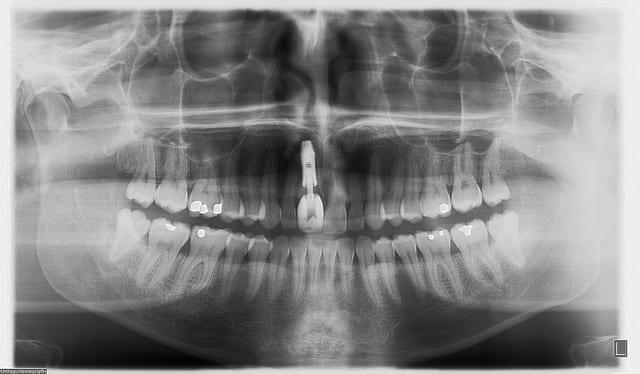

çà manque un peu de cas en ce moment...alors en voilà un ptit au passage...

11 avec résorption interne

EII avec MCI sur du dentium (4.5/14) comblement du gap vestibulaire avec du kasios tcp (très constant dans les résultats...et très économique)

pas de photos de chir par contre...j'ai du les effacer par erreur...grrrr...

la prothèse d'usage a été réalisée par ma petite associée...mais j'étais là pour superviser et faire quelques photos...;-)